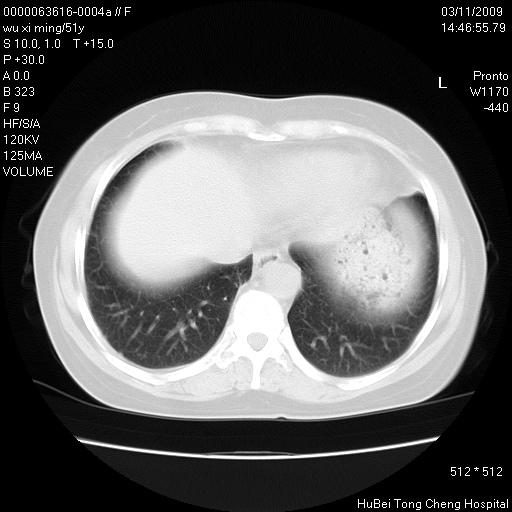

患者 女,51岁。因“胆囊炎,胆囊结石”,行常规术前胸部x线检查发现:右上肺结节病灶,建议行进一步检查。患者无咳嗽、咳痰及咯血等呼吸道症状,近期出现背部疼痛不适。

胸部ct轴位平扫(层厚10mm,螺距1.5,重建间隔10mm;部分层面:层厚3mm,螺距1.0,重建间隔3mm),图像如下:

1、周围型肺癌。(毛刺正、血管束集征,分叶。)

集束征,胸膜牽拉征,毛刺,淺分葉高度提示ca.

右肺周围型肺癌伴肺内转移及胸椎转移。已无手术机会。